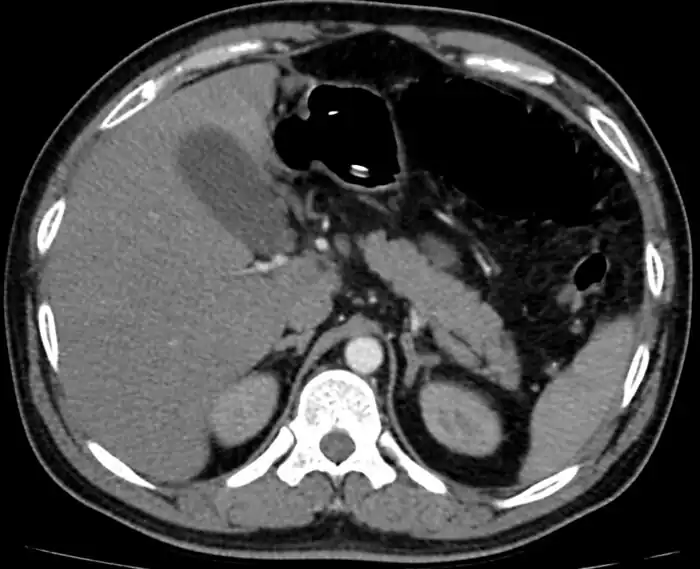

Mesenteric ischemia/CT image

Mesenteric ischemia